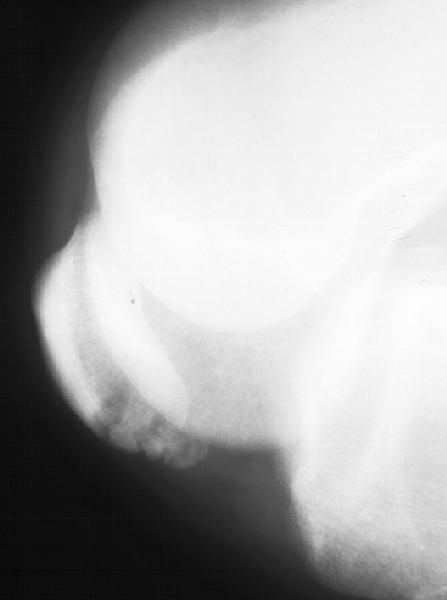

Мужчина 33 лет поступил через 2 недели после автоаварии (был за рулем) с переломом бедра. На этой же стороне есть перелом нижнего полюса надколенника. Клинически отека и гемартроза нет, интенсивная пальпация слабо болезненна прямо над линией перелома. Пальпаторно разгибательный аппарат сохранен. Бедро вчера синтезировано стержнем. Сделал сразу после этого снимок в полном сгибании - ничего никуда не расходится, и у меня рука не поднялась. Есть ли настоятельная необходимость оперативной фиксации, и если да, то чем?